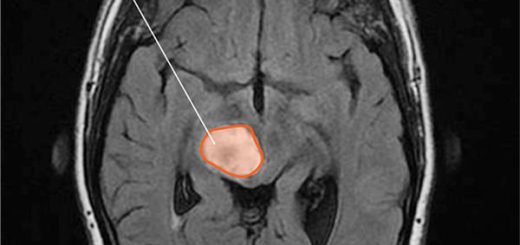

Barbosa ve ark. glioma, meningioma, oligodendroglioma ve kraniofaringioma gibi beyin tümörlerinde AChE ve BChE aktivitelerini araştırmış adı geçen bütün beyin tümörlerinde her iki kolinesteraz aktivitesini pozitif bulmuþtur.